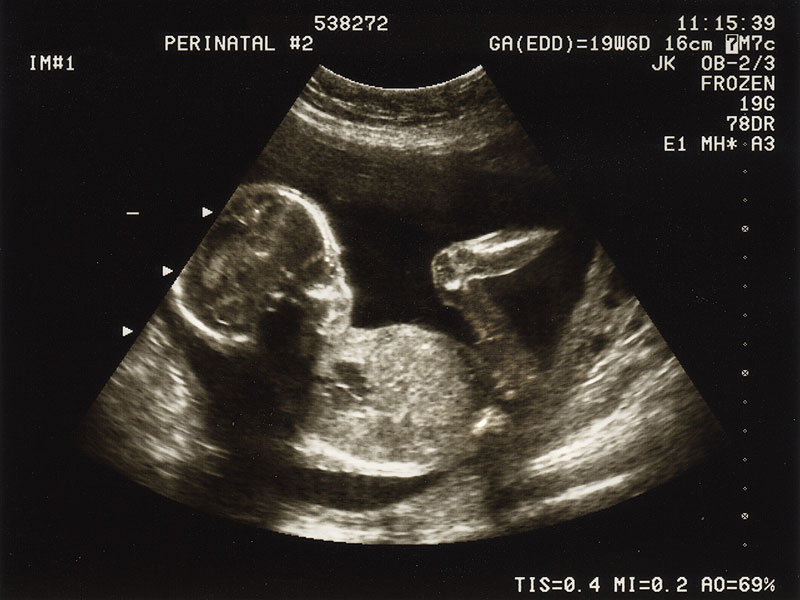

یک سونوگرافی که بین هفته های 18 تا 22 بارداری انجام می شود، اطلاعاتی را در مورد جنبه های مختلف بارداری به زن باردار و مراقب او می دهد. سونوگرافی مامایی تعداد جنین های حاضر، سن حاملگی و محل جفت را به آنها اطلاع می دهد و/یا تایید می کند. این فرصتی برای تشخیص ناهنجاریهای مادرزادی و/یا شناسایی نشانگرهای نرم آنیوپلوئیدی و شناسایی آسیبشناسی لگن مادر ارائه میکند

اکنون کودک شما به اندازه کافی بزرگ شده است تا بتواند نگاه دقیقی به کودک خود داشته باشد. سونوگرافی هفته 18 تا 22 چگونگی رشد و تکامل کودک را بررسی می کند. این سونوگرافی می تواند اطلاعات زیادی در مورد بارداری ارائه دهد، از جمله:

نحوه رشد اندام ها و ساختارهای داخلی کودک (مانند قلب، مغز، کلیه ها، ستون فقرات، بازوها و پاها)

آیا اندازه کودک برای سنش مناسب است یا خیر

موقعیت نوزاد

کودک چقدر فعال است

مقدار مایع اطراف نوزاد

محل جفت و بند ناف

دهانه رحم، رحم، تخمدان ها و مثانه خودتان

جنسیت کودک، بسته به موقعیت کودک. بررسی جنسیت نوزاد از اهداف این سونوگرافی نیست.